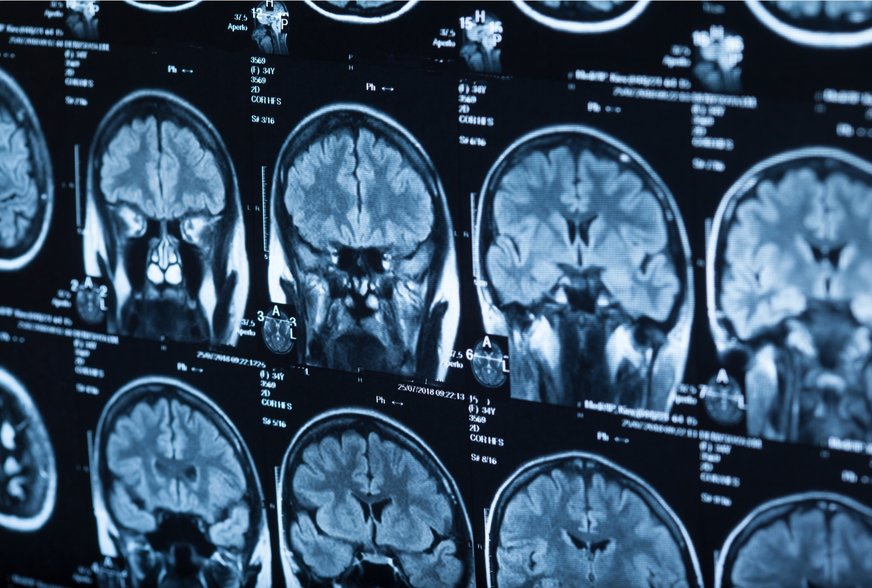

Glioblastóm je jeden z najagresívnejších typov rakoviny mozgu. Pre mnohých je šanca na prežitie nízka. Nový typ terapie mozgového nádoru, ktorý chce rakovinu „vyhladovať na smrť“, by však mohol pomôcť zmeniť veci k lepšiemu. Nová štúdia izraelských vedcov ukazuje, že glioblastóm sa spolieha na špecifické mozgové bunky, ktoré podporujú rast nádorov. Tím preto začal hľadať spôsoby, ako liečiť rakovinu odstránením týchto buniek. Ich terapia by mohla úplne vyhladovať rakovinové bunky a umožniť pacientom vstúpiť do remisie.

Bežne by lekári použili chemoterapiu priamo zameranú na nádor. No výskumníci zistili, že odstránením mozgových buniek nazývaných astrocyty môžu vyhladovať glioblastómové nádory u myší. Nádory sa znovu neobjavili, kým boli astrocyty potláčané. Dr. Lior Mayo, hlavný autor štúdie, hovorí, že aj keď ich prestali potláčať, 85 percent myší zostalo v remisii. Všetky myši v štúdii, u ktorých nechali astrocyty aktívne, uhynuli.